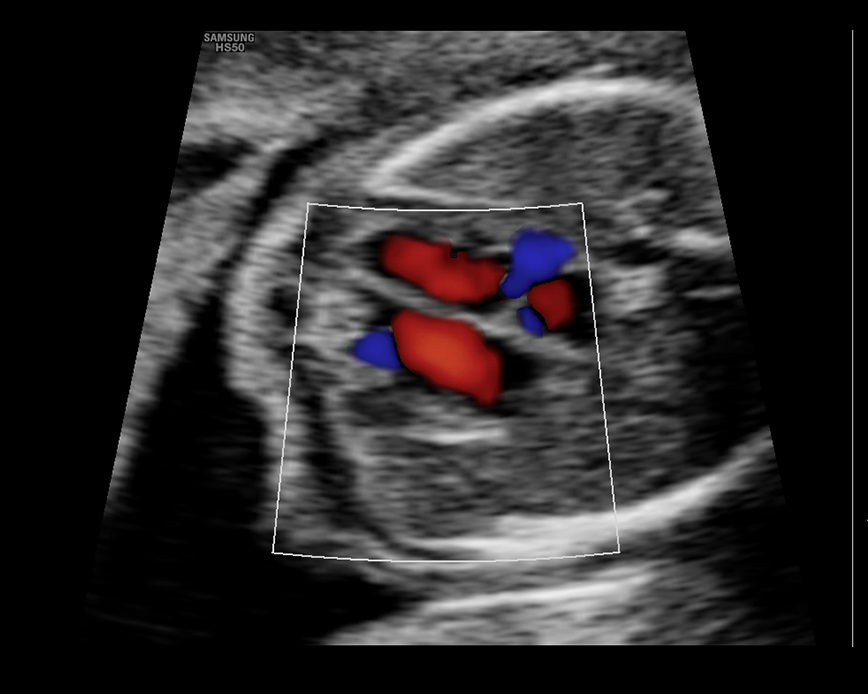

Esta ecografía sirve para evaluar la hemodinamia materno-fetal y detectar problemas de crecimiento como el RCIU (Restricción del Crecimiento Intrauterino) y el riesgo de preeclampsia (presión arterial alta durante el embarazo). Además, nos permite evaluar el cordón umbilical y detectar circulares de cordón simple, doble o triple.